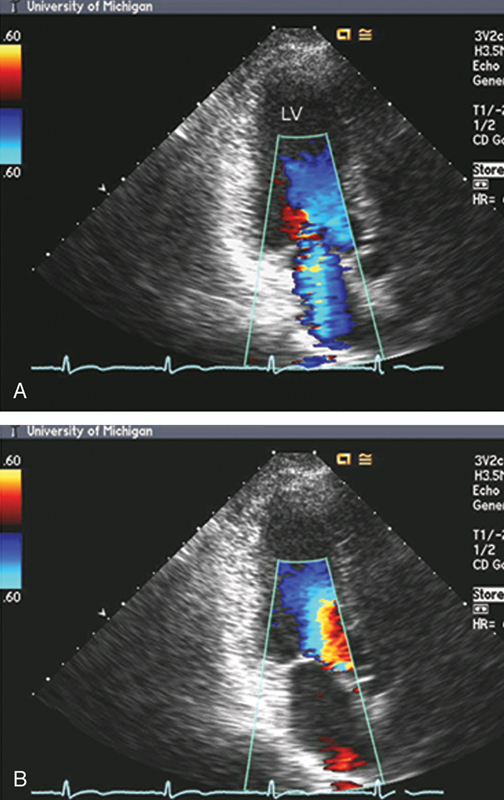

فحوصات تشخيصية لبعض امراض القلب والشرايين التاجية